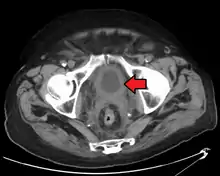

| Transitional cell carcinoma of the bladder. The white in the bladder is contrast. | |